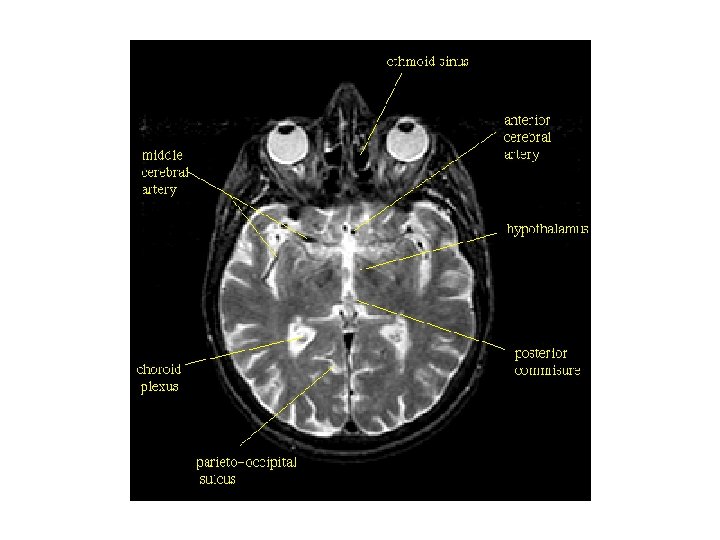

뇌 기저면(basal surface)의 동맥분포 1. 전대뇌동맥(anterior cerebral artery) 2. 전교통동맥(anterior communicating artery) 3. 내경동맥(internal carotid artery) 4. 중간대뇌동맥(middle cerebral artery) 5. 전맥락동맥(anterior choroidal artery) 6. 후교통동맥(posterior communicating artery) 7. 후대뇌동맥(posterior cerebral artery) 8. 상소뇌동맥(supeior cerebellar artery) 9. 뇌기저동맥(basilar artery, 뇌저동맥) 11. 전하소뇌동맥(anterior inferior cerebellar artery, AICA) 13. 후하소뇌동맥(posterior inferior cerebellar artery, PICA) 15. 전척수동맥(anterior spinal artery) 10. 교뇌동맥(pontine branches) 12. 미로동맥(labyrinthine artery) 14. 척추동맥(vertebral artery)